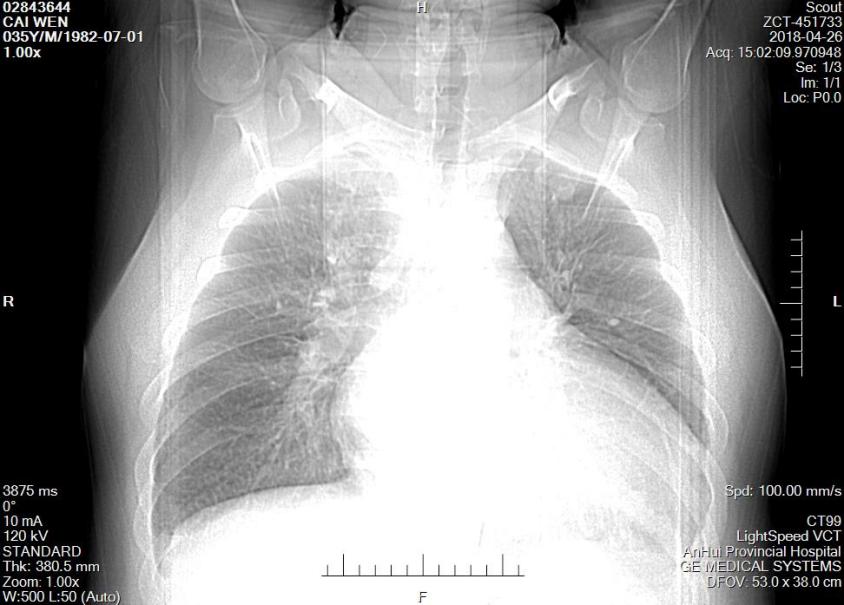

▎ 胸片:心影增大、肺部感染。

图2:患者入院胸片